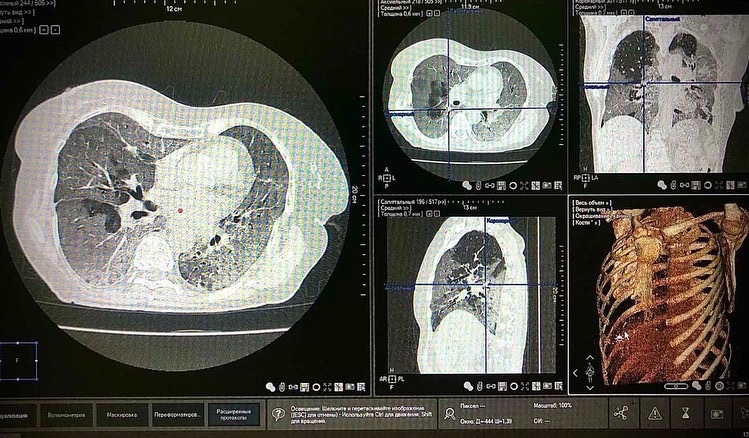

Представлены данные КТ легких с 80% поражением и для сравнения - без поражения. Пациентка 63 лет с коронавирусной инфекцией, находящаяся в тяжелом состоянии с выраженной дыхательной недостаточностью, не была привита. Не доводите себя до такого состояния, сделайте прививку, не рискуйте жизнью. Берегите себя и своих близких!